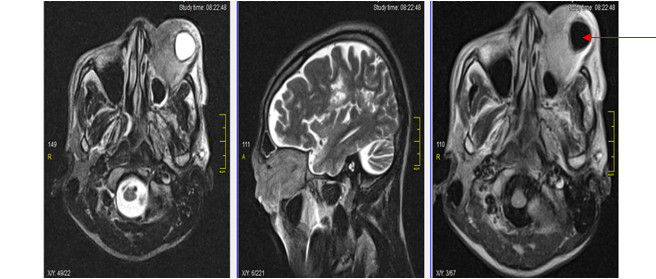

Volver a los detalles del artículo Linfoma primario de la órbita. Informe de un caso